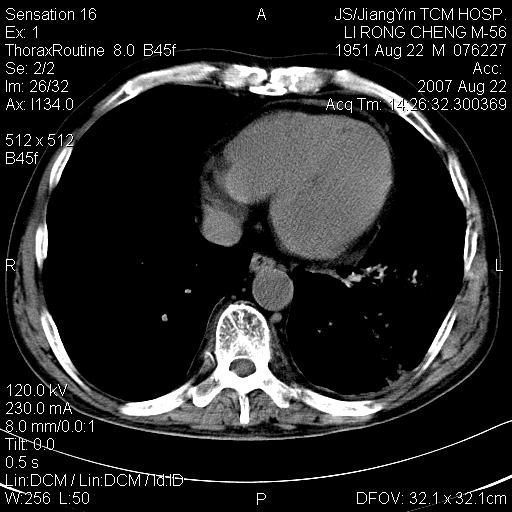

标题: CT9479:M,56Y,DM病史,咳嗽发热5天.肺脓疡.肺癌? [打印本页]

标题: CT9479:M,56Y,DM病史,咳嗽发热5天.肺脓疡.肺癌?

边灶边缘较光整,冠状位病灶呈大片状,,内有空洞,有胸膜反应,但无明显胸膜外侵犯征像,结合病史支持考虑肺肿脓,不排除结核,治疗后复查

好多钙化灶哦,病灶位于下叶背段,或许考虑结核更合适,做下相应检查先

左肺下叶见类软组织密度影,其内密度不均,有小空洞,广基与胸膜相连,其周见斑片状致密影.

考虑肺肿脓,不排除结核.

左肺下叶支气管呈小囊状扩张。下叶背段有类圆形高密度影,边缘模糊,外与胸膜相连。左侧胸膜增厚粘连。心包膜增厚。结合病史考虑1支扩并感染2胸膜及心包炎。

左下肺团片状类软组织密度影,形态不规则,边缘欠规整,其内可见液化区及气体影,病灶内侧见引流支气管影,相邻胸膜反应性增厚。病灶周围肺野内见增粗支气管,壁厚,边缘模糊。考虑:支气管扩张并感染;肺脓肿。